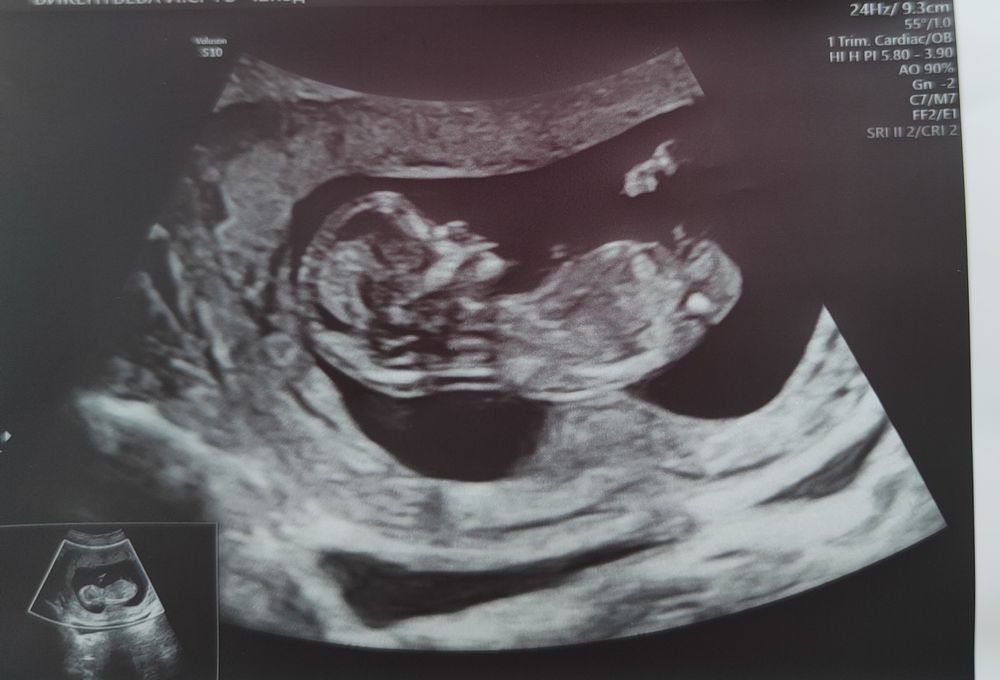

Беременность- 1 триместр ( только до 10 недель)Девочки, больше переживала. УЗИ все хорошо без патологий.. правда пришлось походить и поесть сладкое, а то не давался "новенький" померить себя..напоила его какао сверху банан закинула и утихомирился..дал узисту измерить себя..КТР-63 мм, ровно 12-13 недель ставят, а по месикам-12+3...Ждём кровь теперь, дня 2-3 результаты будут готовы. Если не позвонят то все ок, если позвонят назначат НИПТ( бесплатно ).

Вот наш карапуз .совсем человечек ❤️😍❤️